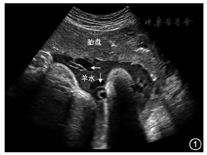

表现为羊水内充满致密的点状强回声,呈云雾状,见图1。常见于孕晚期,多为孕36周后。羊水中内容物可为胎脂或胎粪,文献报道,60%~95%的孕晚期羊水回声增强为胎脂所致;在回声增强的羊水的衬托下,脐带内的无回声可清晰显示[1]。